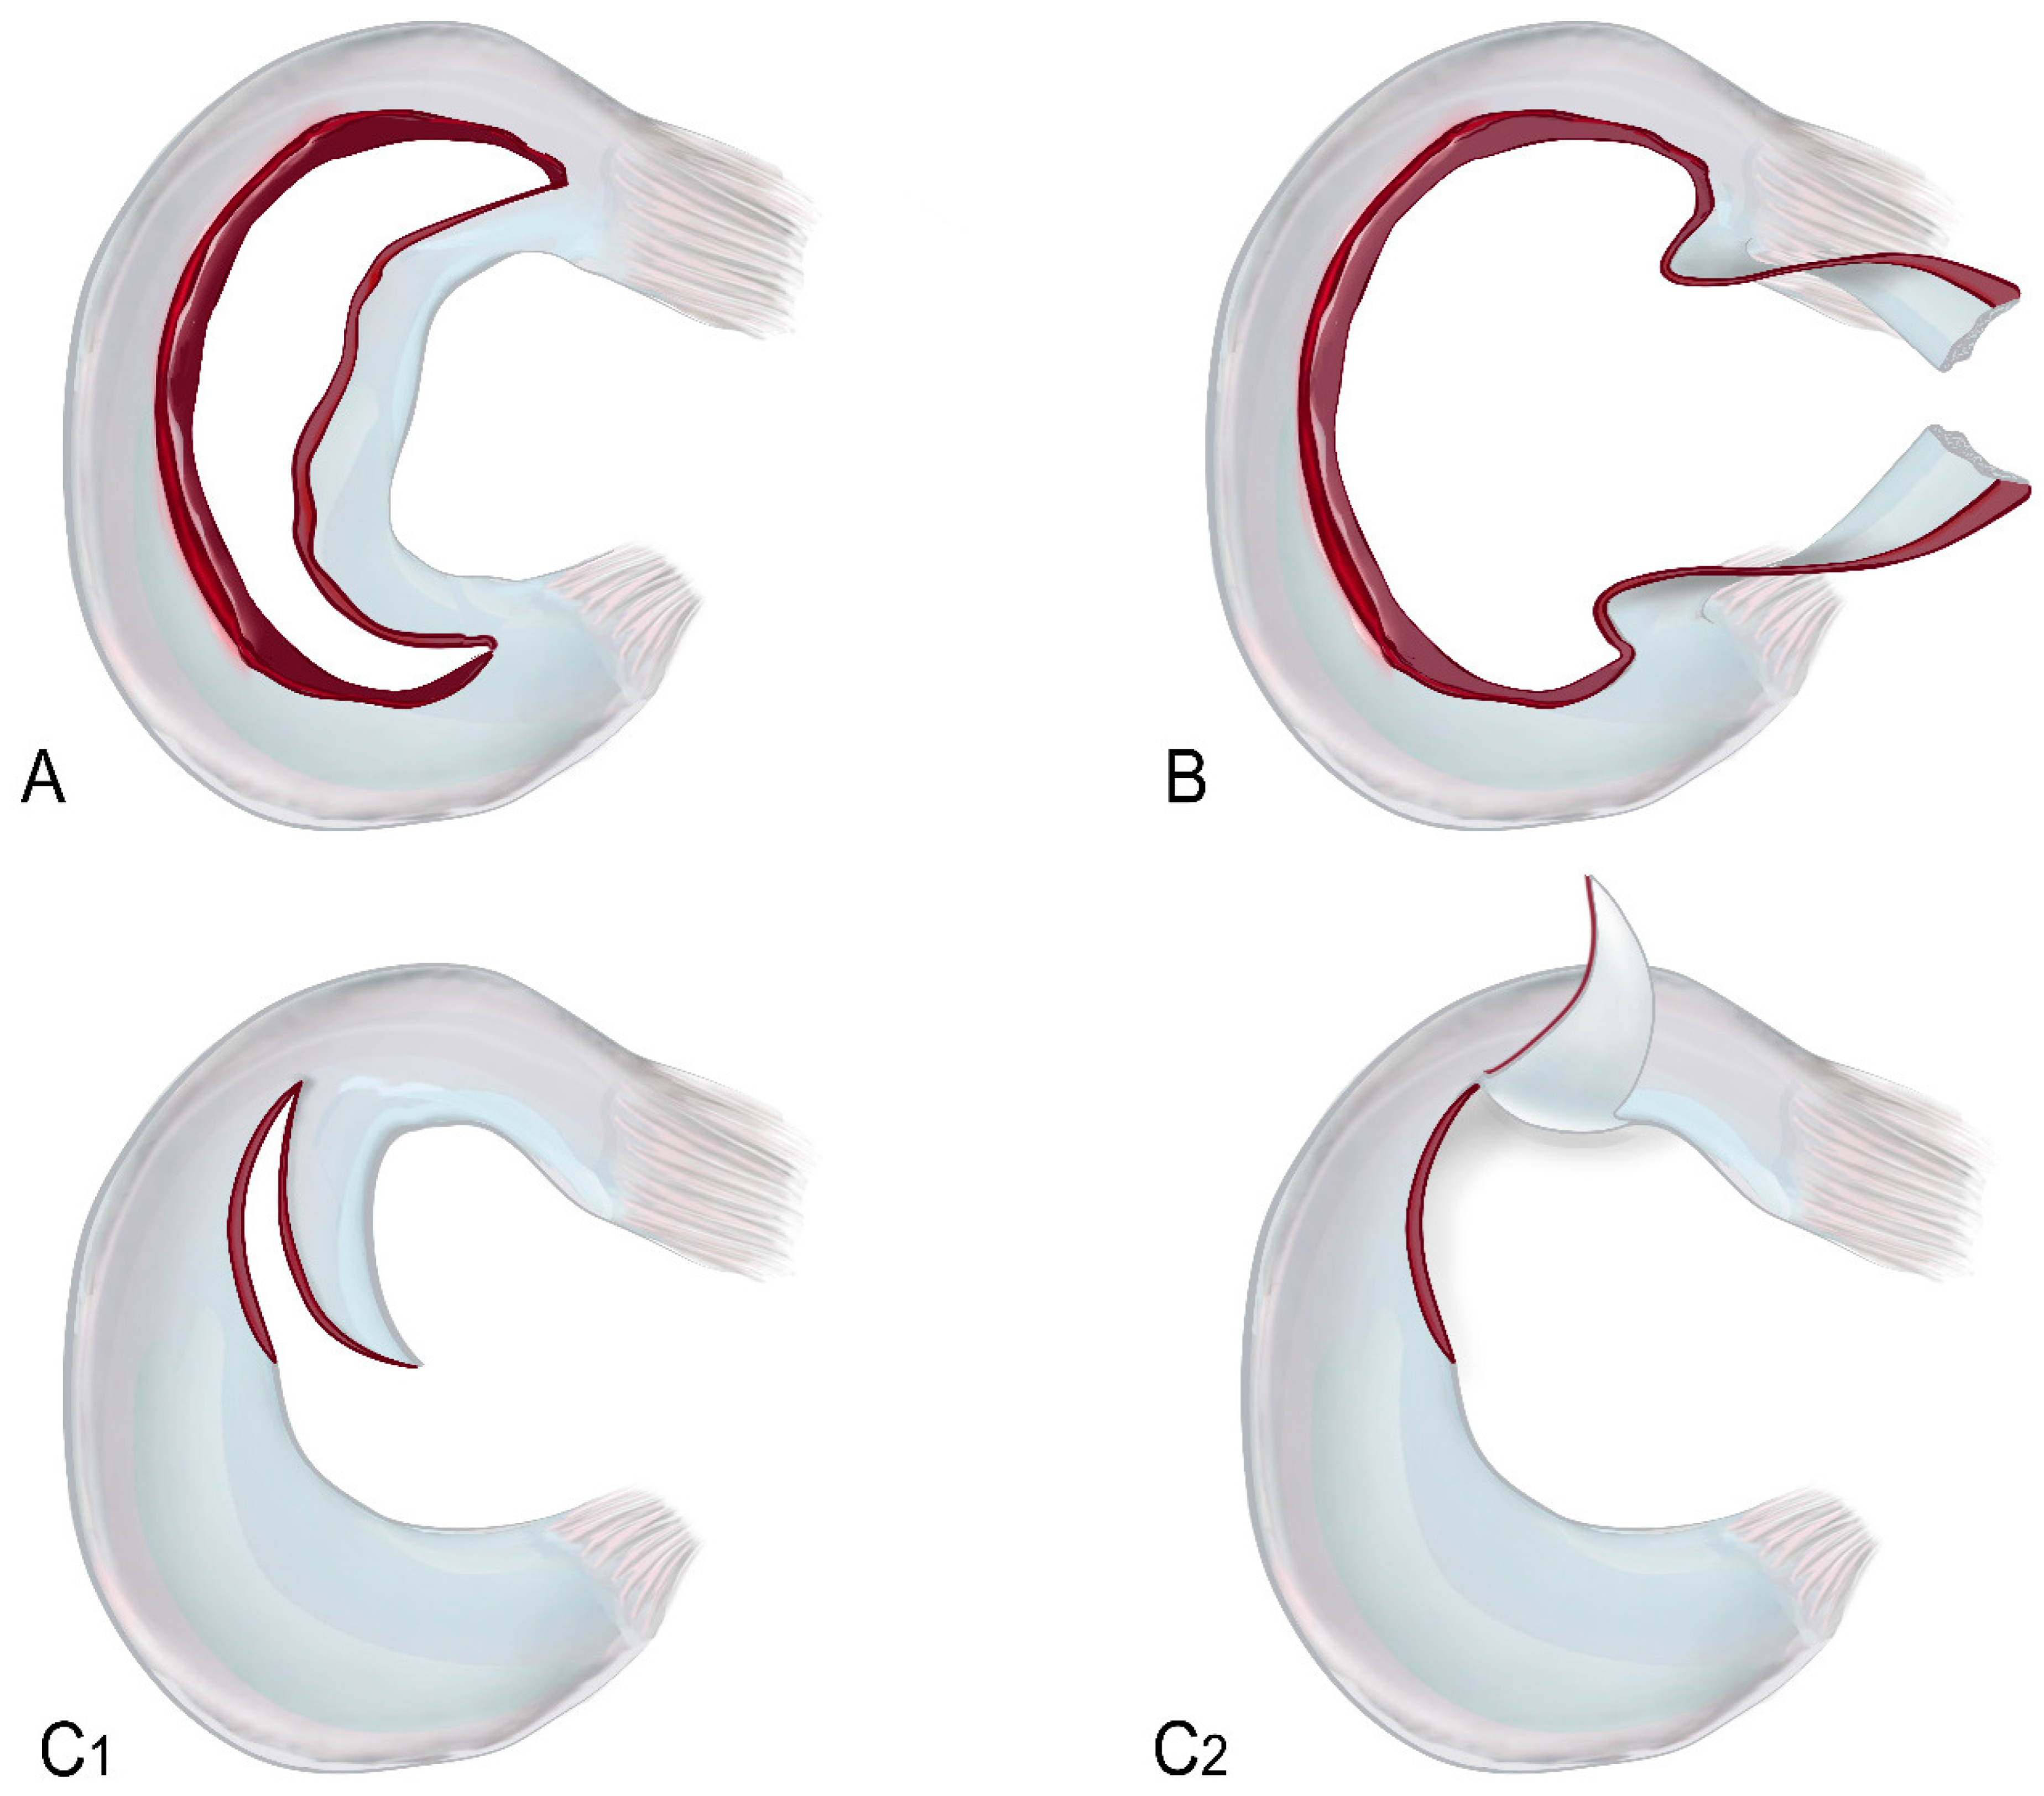

- Tear patterns might be horizontal, radial, vertical flap, horizontal flap, longitudinal–vertical (which incorporates a bucket-handle tear as an extension), or complex. With the exception of complex tears, which include two or more tear patterns, the main tear pattern should be mentioned.

3.1. Medial Meniscus Flap Under the Medial Collateral Ligament

3.2. Medial Meniscus Radial Tear with Flipped Body

3.3. Medial Meniscus Posterior Root Tear with Extrusion

3.4. Lateral Meniscus Flap in Popliteus Recess

3.5. Lateral Meniscus Flipped in the Lateral Gutter

3.6. Lateral Meniscus Posterior Root Tear with Extrusion

3.7. Lateral Meniscus Body Within Tibial Plateau Fracture